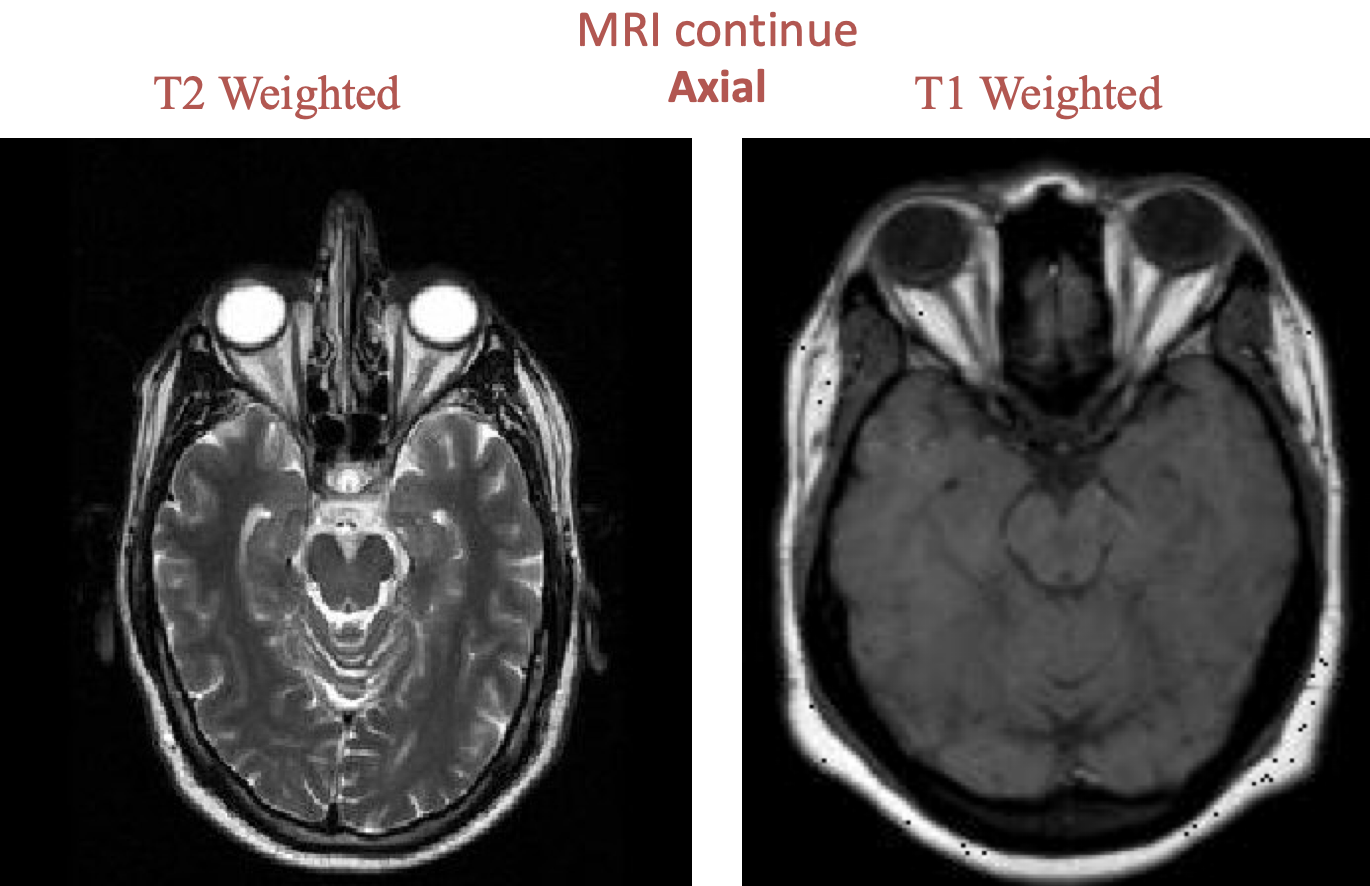

Water appears hypointense in T1 weighted images but hyperintense in T2 weighted images! WW2: “Water looks white in T2” #z

| Sequences | Hyperintense | Hypointense |

|---|---|---|

| T1-weighted | Fat, adipose tissue (white brain matter) Contrast media | Water (CSF, edema ) Bone Ligaments, tendons Air (no signal) |

| T2-weighted | Water (CSF, edema ) Fat (less hyperintense than in T1) | Bones Ligaments, tendons Air (no sign |